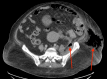

Necrotizing soft tissue infections are aggressive infections that cause necrosis of muscle, fascia, and tissue. They typically follow fascial planes that lack insufficient blood supply. Early drainage and debridement are essential for survival in these patients. This is a case of a patient who presented in diabetic ketoacidosis with a necrotizing soft tissue infection localized to the left flank and abdomen with underlying colon cancer pathology. The patient was a 54-year-old female who initially presented with acute dyspnea and left flank pain for two weeks. On admission, she was afebrile, tachycardic, tachypneic, and hypertensive. After being transferred to the ICU for diabetic ketoacidosis management, she began complaining of left abdominal pain and the CT showed concerns for a possible necrotizing soft tissue infection in the left flank region. She was taken to the operating room immediately for debridement and started on broad-spectrum antibiotics. The next day, an exploratory laparotomy was performed with a hemicolectomy and creation of an end colostomy due to concern for a perforated colonic malignancy. A final debridement was completed and a wound vacuum-assisted closure (VAC) was placed. Final pathology demonstrated well-differentiated colonic adenocarcinoma invading into the muscularis propria. Overall, necrotizing soft tissue infections can be related to a perforated viscus especially a colonic malignancy and this case demonstrates the importance of proper surgical management and high clinical suspicion for possible underlying pathology in a soft tissue infection.